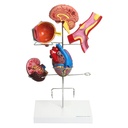

Modell der Hypertonie-Folgen

6-teilig, auf stabilem Gestell mit Kunststoff-Sockel

Zeigt die Folgeerkrankungen des Bluthochdrucks

Anatomische Strukturen sind aufwändig koloriert

Einzelne Organe bei Bedarf abnehmbar

Eignet sich perfekt zur Patientenaufklärung